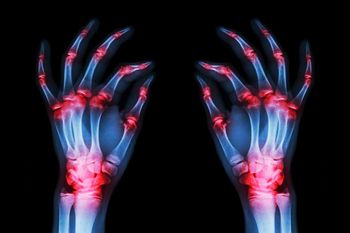

Bone erosions found at a rheumatoid arthritis (RA) patient’s baseline exam are harbingers of future joint damage and more severe disease. As to why this is so, new studies offer only hints.

Evaluating a 29-year-old female business executive with complaints of joint pains and stiffness affecting both hands and wrists, both feet and her left knee. She has reported these symptoms for the past 3 weeks.